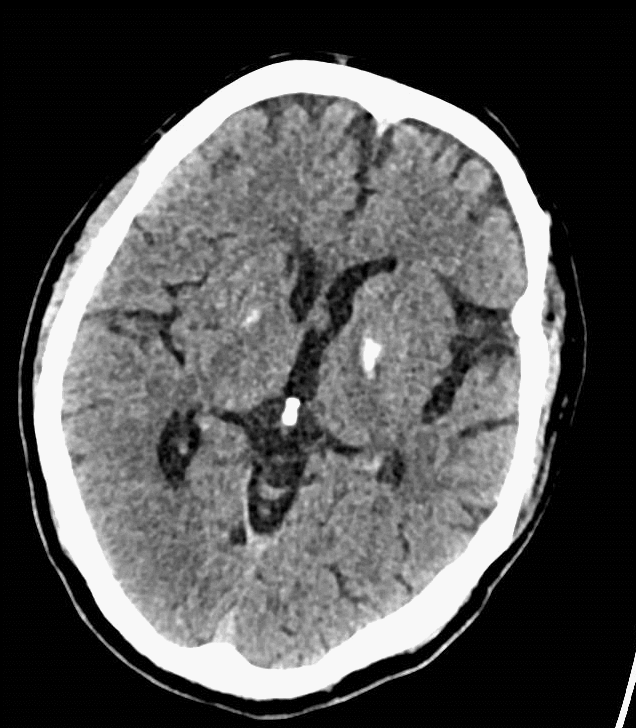

术后复查:颅脑CT平扫未见明显新增脑梗塞。

什么叫桡鞘【例久弥新】寻道于桡——瑞康通5.5F Introsky X导管鞘经桡取栓一例_https://www.jmylbn.com_新闻资讯_第28张

什么叫桡鞘【例久弥新】寻道于桡——瑞康通5.5F Introsky X导管鞘经桡取栓一例_https://www.jmylbn.com_新闻资讯_第29张

复查颅脑CTA及CTP,改善明显。